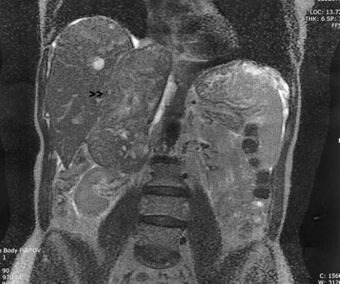

| Leiomyosarcoma of the adrenal vein. Coronal view of abdominal MRI. Tumor (arrow) extends from the superior pole of the right kidney to the right atrium. |